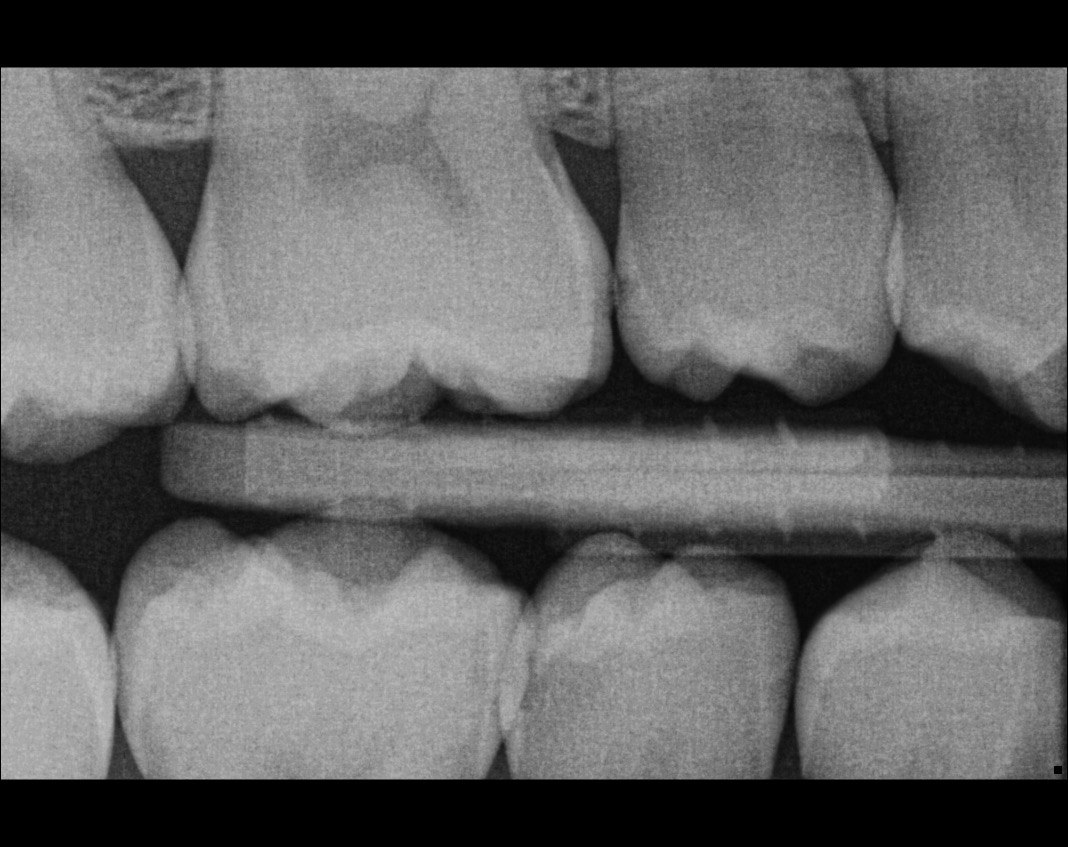

41. What options can be selected for the following X ray?

42. What is the caries on mesial surface of the tooth # 3.6?

43. Which surfaces require restoration?

44. What is the condition on distal surface of the tooth # 4.4?

45. What is the condition on mesial surface of the tooth # 1.5?

46. which teeth shows evidece of occlusal recurrent caries?

47. Which option does not describe the X ray bellow correctly?

48. Which tooth shows recurrent caries?

49. Which surface shows a RA1 caries?

50. Which option is evident on the print of the X ray?